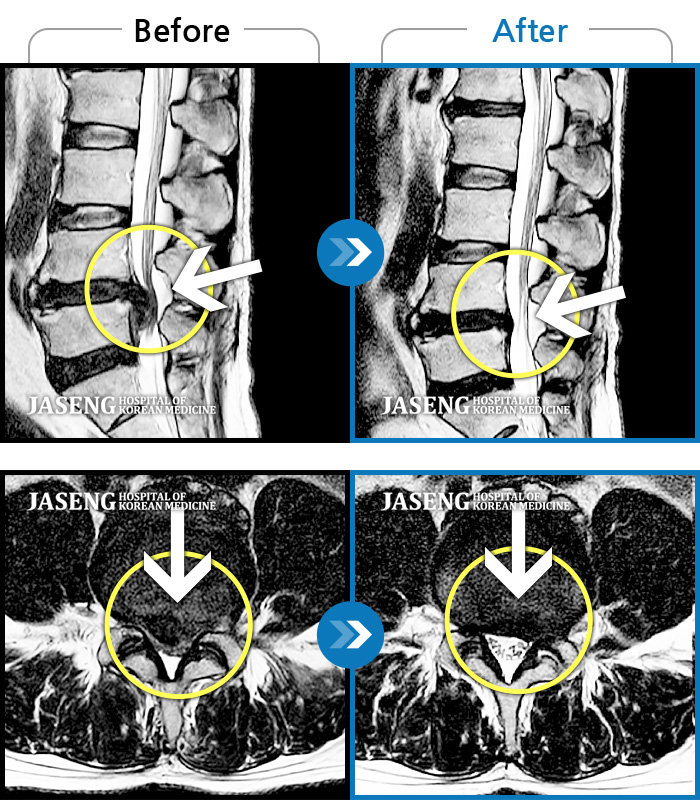

허리에서 왼쪽 다리, 발까지 저리고 왼쪽 발목, 엄지발가락 힘이 안들어가요.